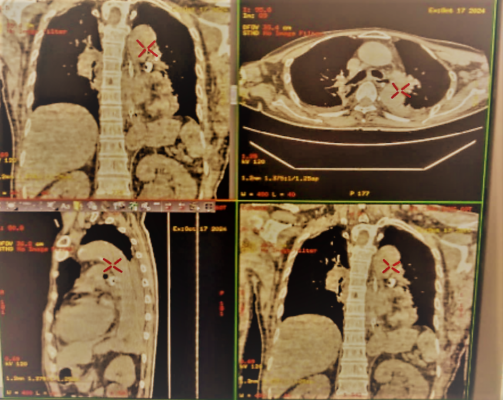

Bệnh nhân nam giới – 60 tuổi, có tiền sử teo não, vào khoa hồi sức trong tình trạng khó thở, suy hô hấp. Bệnh nhân được chỉ định chụp cắt lớp lồng ngực và đã phát hiện trong lòng khí phế quản tại thùy dưới trái bệnh nhân có dị vật.

BSCKI Nguyễn Hữu Hạnh cùng ekip nội soi đã tiến hành nội soi phế quản ống mềm có gây mê để khảo sát toàn bộ đường thở của bệnh nhân. Khi đưa ống nội soi đến phế quản thuỳ dưới phổi trái, phát hiện một dị vật to bằng đầu ngón tay út, có nhiều góc cạnh, đờm và mủ bao phủ bên ngoài, dị vật che lấp gây tắc hoàn toàn phế quản S8, S9, S10 trái. Ngoài ra, dị vật di động theo nhịp thở, cọ vào thành phế quản gây chảy máu trong lòng phế quản. Ekip nội soi đã tiến hành các kỹ thuật lấy dị vật thông qua nội soi khí phế quản bằng ống mềm, dị vật là một răng rụng.

Dị vật phế quản thùy dưới trái Hình ảnh dị vật sau khi được lấy ra